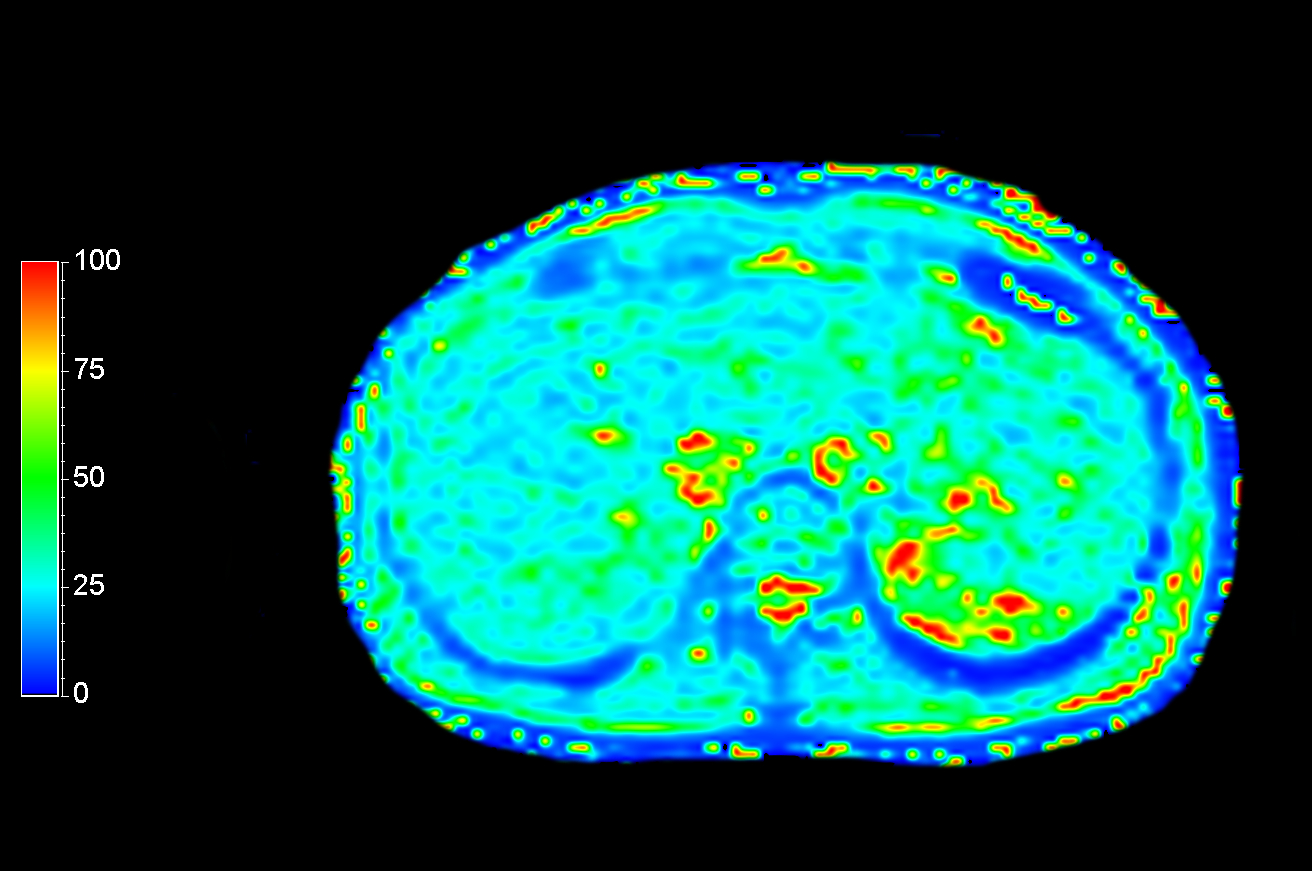

Axial mDIXON Quant (Fat fraction)